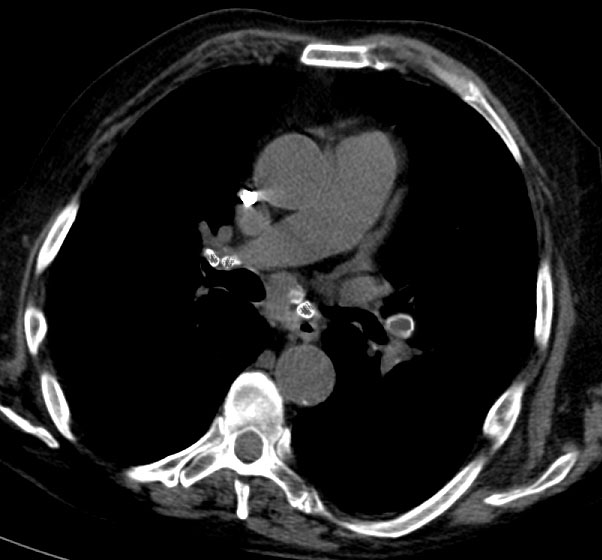

SIGNO DEL HILIO TAPADO u OCULTACIÓN HILIAR

Signo visible en la radiografía posteroanterior de tórax que permite reconocer si una masa es hiliar o mediastínica. Cuando la masa es hiliar está en contacto con la arteria pulmonar y la borra. En cambio, cuando vemos la masa superpuesta a la arteria pulmonar (flechas) sin borrarla, entonces la lesión no es hiliar, sino que se sitúa anterior (más comúnmente) o posterior al hilio. La imagen corresponde a una paciente con un linfoma, es decir,una masa mediastínica anterior.

La radiografía lateral de tórax confirma la localización anterior de la lesión.

Otro ejemplo del signo del hilio tapado, esta vez correspondiente a un carcinoma tímico superpuesto al hilio izquierdo (flecha).